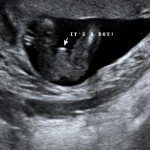

Baby Boutique and gender reveal party supplier.

Our baby boutique offers many unique items to announce the gender of your little one. We offer confetti cannons, powder cannons, flutterfetti sticks, and smoke bombs. We also have a variety of infant outfits and blankets. Our boutique features ultrasound photo frames and unique frames and gifts for grandparents. Record your baby’s heartbeat in one of our adorable animals for a keepsake you will cherish forever.